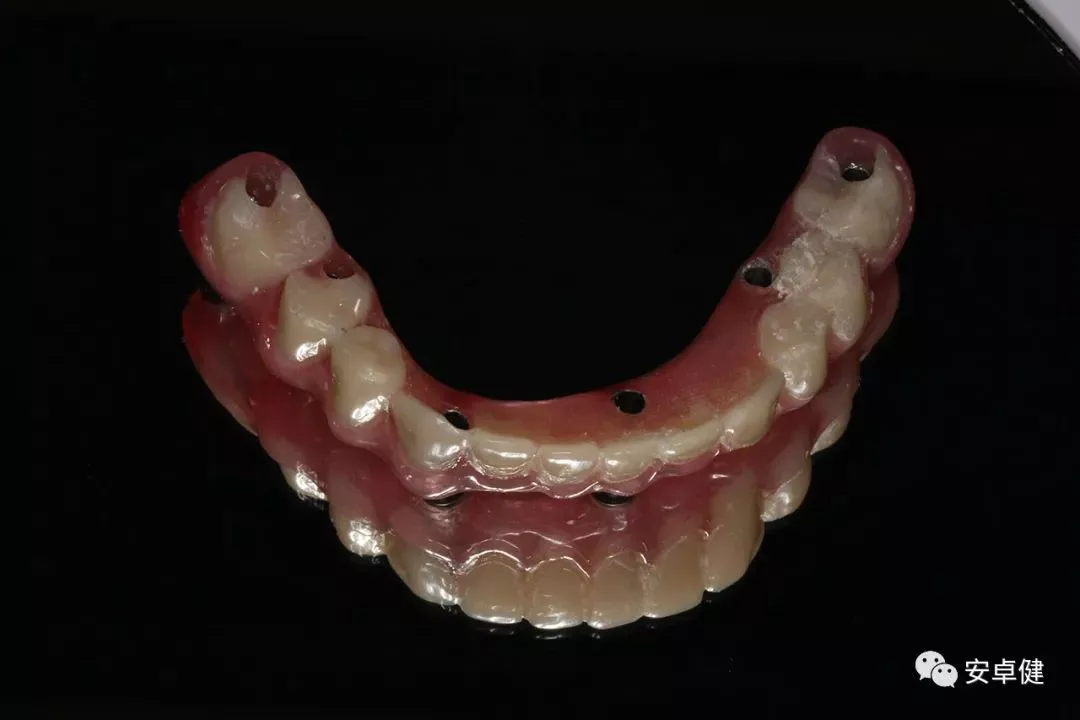

• 完成最终修复体制作。

最终修复体合面照

最终修复体正面照

最终修复体正面咬合照

最终修复体侧面咬合照

• 于口内试戴原厂纯钛切削一体式桥架,并检查前牙排蜡外形及后牙咬合关系;

• 聚合瓷烤塑制作最终修复体;

• 为减少牙面磨耗,于后牙区制作360度防裂纯钛金属带;

• 试戴满意后,二级螺丝加力至15N;

• 特氟龙封闭螺丝孔,光固化复合树脂封闭上方螺丝通道,完成最终固定式种植义齿修复;